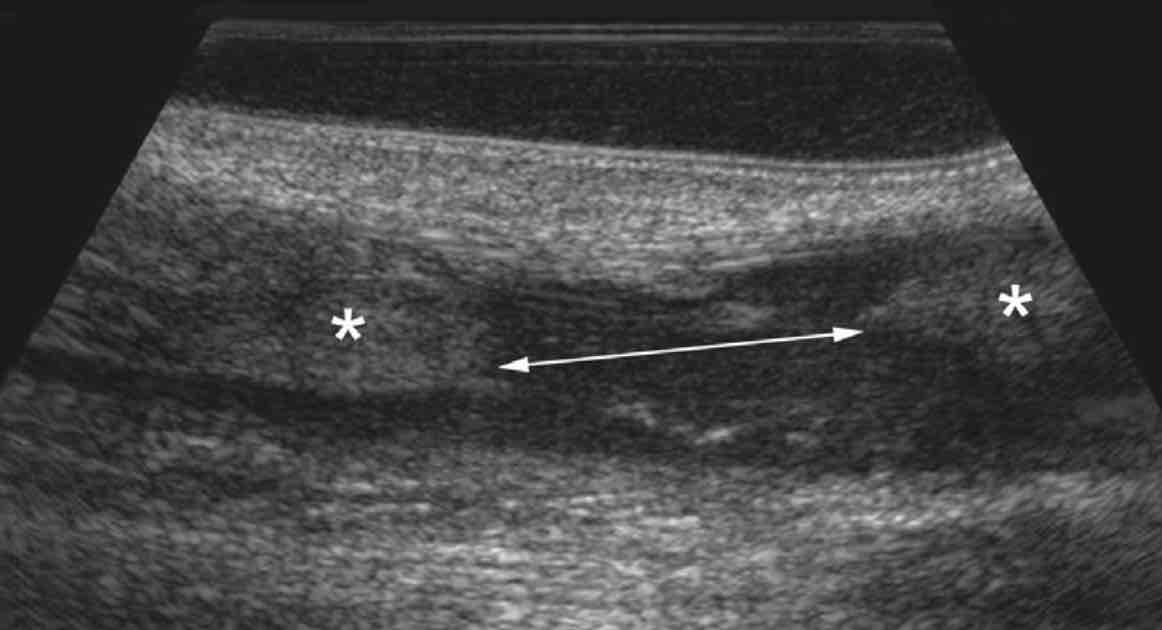

Pas d'épanchement dans l'articulation tibio-talienne.

Aspect normal des ligaments talofibulaire antérieur et calcanéofibulaire.

Respect des ligaments talonaviculaire dorsale, tibiofibulaire antéro-inférieur et calcanéocuboïdien latéral.

Comblement graisseux hyperéchogène sans particularité du sinus du tarse.

Tendons court et long fibulaires en place, sans épanchement.